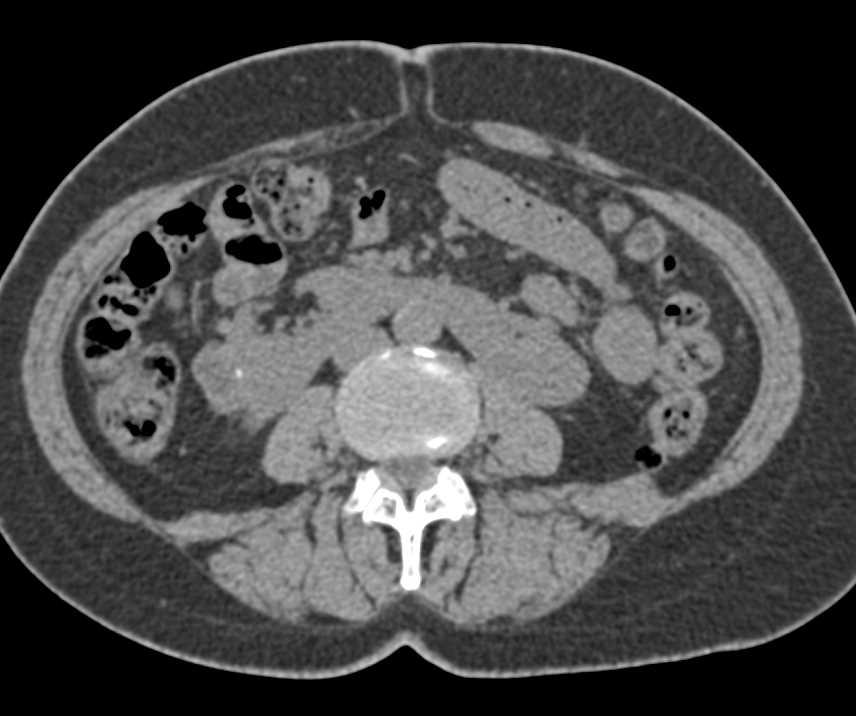

Duplicated Collecting System Right Kidney with Obstruction